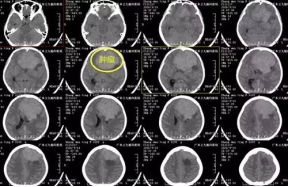

张女士,20岁,因间断头痛伴恶心、呕吐1年余,加重伴右侧肢体麻木1月,为求治疗,来我院就诊。入院后行头颅CT及MR示左侧额部大脑镰旁巨大脑膜瘤,大小约7.8×7.5×7cm,术前CTA提示肿瘤血管丰富,左侧大脑前动脉受挤压明显。由于瘤体太大,为保证患者的手术安全,经科室专家讨论研究决定,择期全麻下为患者行“左侧额部大脑镰旁巨大脑膜瘤切除术”,手术由张良主任主刀完成。经手术、术后康复理疗、物理治疗等系统的治疗后患者症状消失,康复出院。

↑术前检查